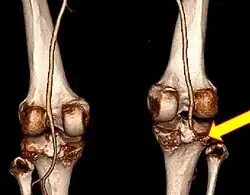

| Plain lateral X-ray of the left knee showing a posterior knee dislocation[1] | |